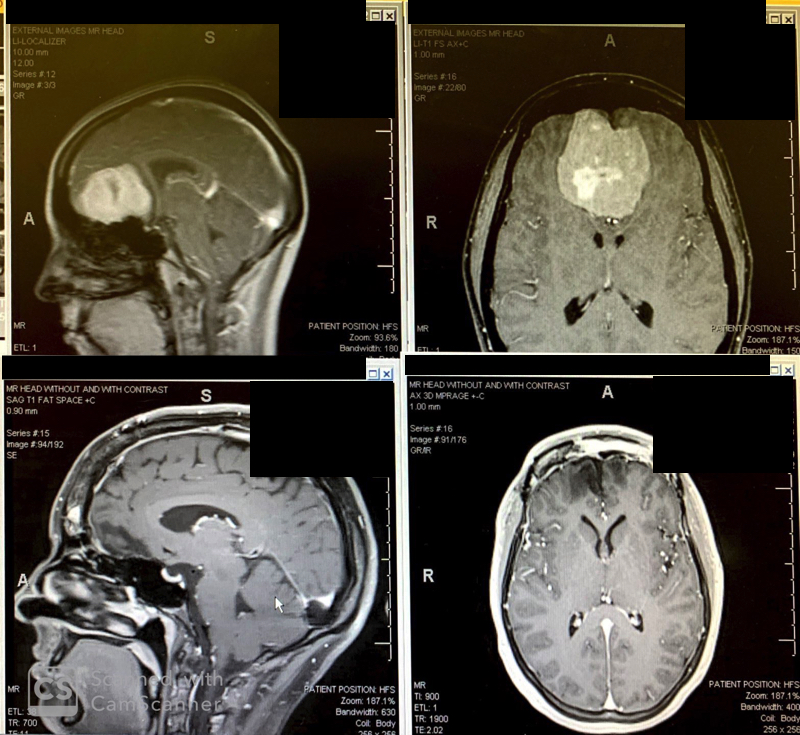

Top and bottom left: brain tumor before surgery. Bottom right: after stereotactic radiosurgery.